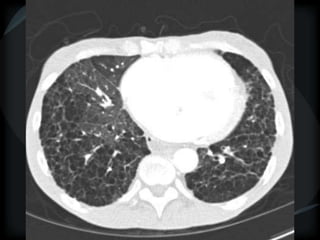

Sarcoid

perilymphatic